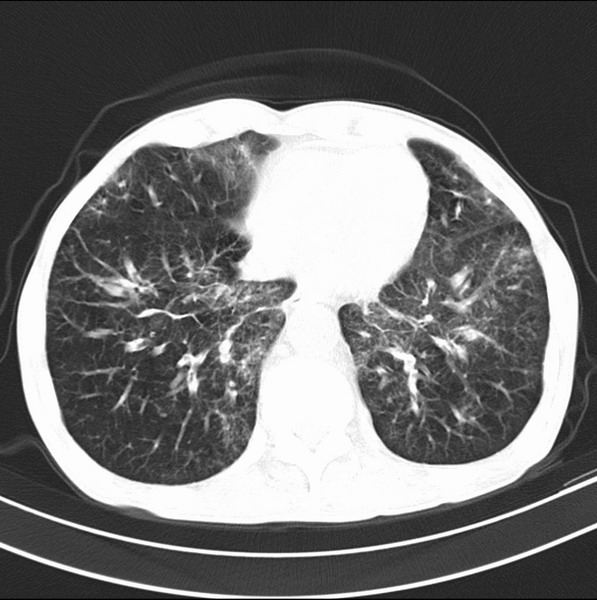

标题: CT19600:能否诊断为转移?

女、55

3年前盲肠癌、一年半前诊断膀胱癌,现在呼吸困难,临床考虑为肺转移

请问胸部ct如何诊断?能否排除淋巴管炎,纵隔窗没有问题。

考虑间质性病变,癌性淋巴管炎可能.

转移,癌性淋巴管炎。

建议抗炎后复查,不除外癌性淋巴管炎。

考虑间质性病变,癌性淋巴管炎可能.支持!

支持考虑间质性病变,癌性淋巴管炎可能.